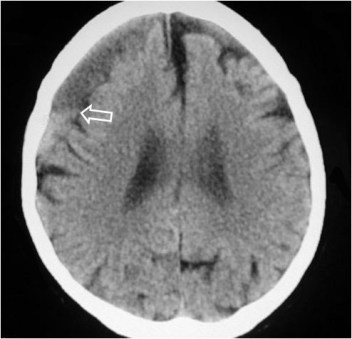

SIGNO DEL HEMATOCRITO

En los hematomas de múltiples localizaciones (espacios sub o epidural, intraventricular, subcapsular hepático, intramuscular,…), aparece, tras un tiempo variable, un nivel líquido-líquido, más denso (en TC) o ecogénico (en ecografía) en la zona declive, debido al depósito de elementos celulares de la sangre.

La imagen corresponde a un paciente con un hematoma subdural subagudo en el que puede verse este signo.